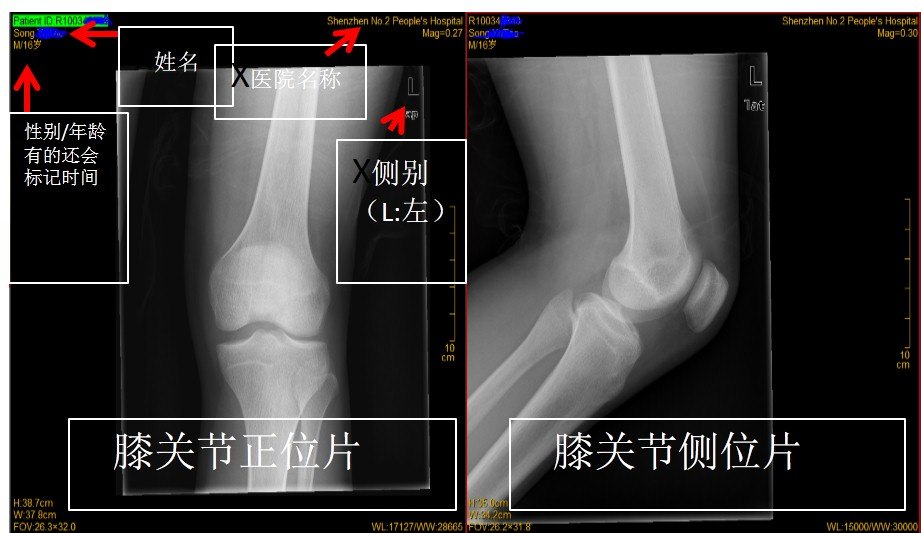

每张片子一般都包含 医院、姓名 、性别、年龄、左右侧别、时间、扫描序列等信息

1.X线片(膝关节为例)

一张膝关节X片一般包括膝关节正位和膝关节侧位片。片子上一般标记有医疗机构、姓名、性别(W:女;M:男)、侧别(L:左;R:右)、时间,其他标记的有标尺、窗口等。